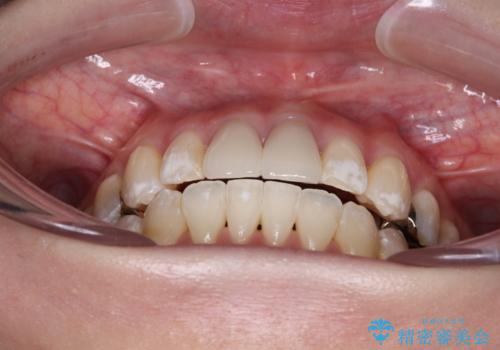

口元が前方に突出することもなく、綺麗に仕上げることができました。